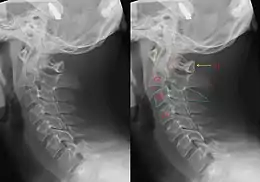

Hangman's fracture

Hangman's fracture is the colloquial name given to a fracture of both pedicles, or pars interarticulares, of the axis vertebra (C2).

The mechanism of the injury is forcible hyperextension of the head, usually with distraction of the neck. Traditionally this would occur during judicial hanging, when the noose was placed below the condemned subject's chin. When the subject was dropped, the head would be forced into hyperextension by the full weight of the body, a sufficient force to cause the fracture. However, despite its long association with judicial hangings, one study of a series of such hangings showed that only a small minority of hangings produced a hangman's fracture.[4]

Although a hangman's fracture is unstable, survival from this fracture is relatively common, as the fracture itself tends to expand the spinal canal at the C2 level. It is not unusual for patients to walk in for treatment and have such a fracture discovered on X-rays. Only if the force of the injury is severe enough that the vertebral body of C2 is severely subluxed from C3 does the spinal cord become crushed, usually between the vertebral body of C3 and the posterior elements of C1 and C2.